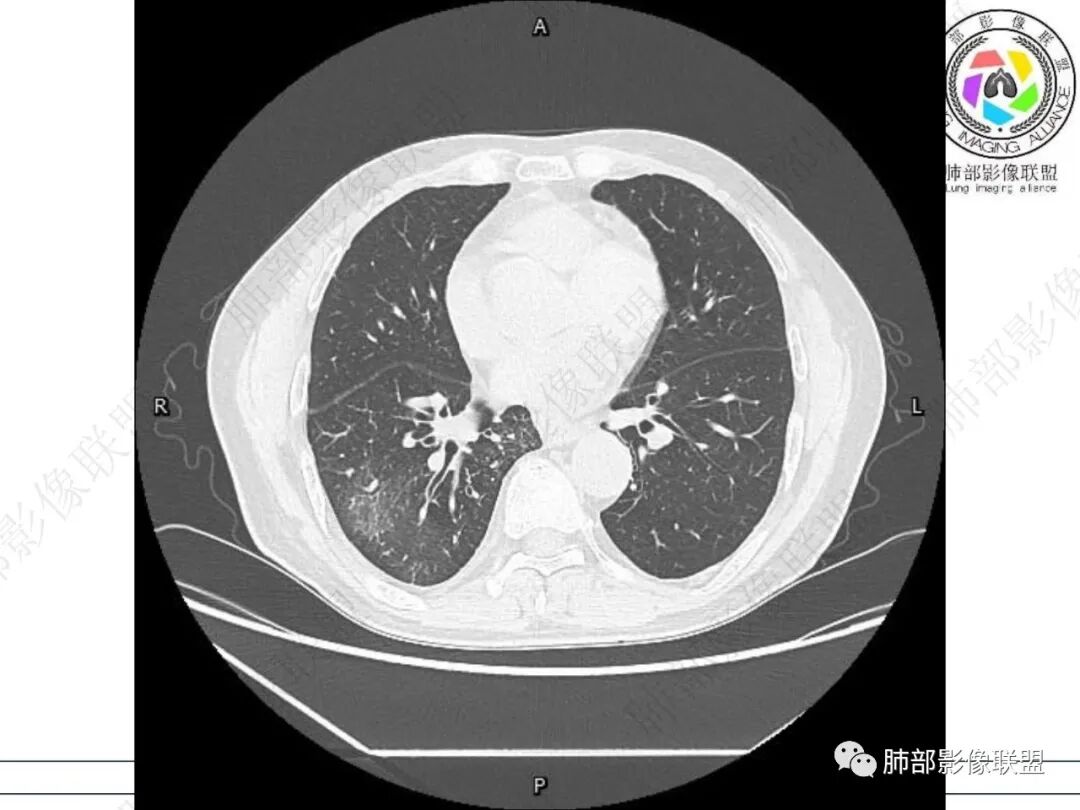

右肺下叶背段可见斑片状、条片状高密度影,支气管扩张,周围伴有磨玻璃影,边界欠清,纵隔窗:可见脊柱偏右侧可见斑片状影,与食管交界面欠清,食管形态不规则,考虑食管支气管瘘?食管异物穿孔?支气管异物?建议食管镜及支气管镜检查。

右肺下叶背段条片状实变影,内可见支气管走行,支气管有狭窄有扩张,周围可见磨玻璃影,隆突下团片影,内密度不均可见气体影,与周围结构界限不清。食管下段壁增厚,管腔狭窄,右肺下叶慢性炎、肺不张,考虑食道肿瘤所致气管食管瘘。

男性69岁,咳嗽,咳痰10多年。两肺下叶有支气管扩张的改变,右肺下叶背段的片状实变阴影,有支气管的扭曲样穿行,有病灶的收缩,以及沿着支气管的 播散病灶,肺门纵隔内支气管隆突的上下呈大片状的实变影,结构比较混乱,食管显示的不清楚,伴有多发的淋巴结增大。临床上主要提及呼吸道的症状,但是没有提及消化道的症状。另外还见到肝内有多发的低密度病灶,考虑囊肿。

右肺下叶沿肺叶肺段分布斑片、条片状影,以下叶背段为显,边缘模糊,内可见支气管走行,局部支气管管壁增厚,右侧胸腔少量积液。纵隔隆突下可见不均匀软组织密度影,与周围结构分界不清,内见气体密度影,与食管及相邻右肺支气管之间未显示通道。邻近食管下段壁明显不规则增厚,增强后食管管壁明显不均匀强化,可见线样强化的连续完整粘膜影。